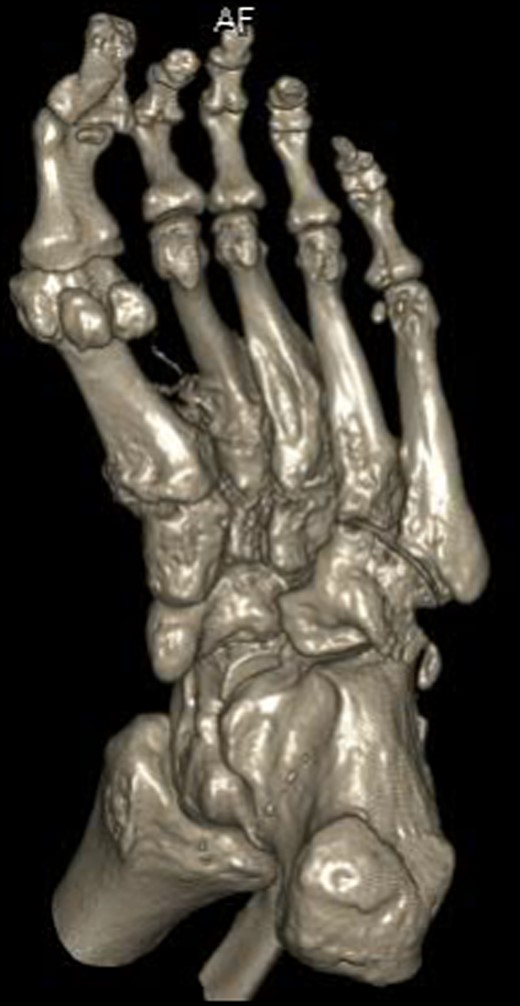

Three-dimensional CT reconstruction of the left foot in the dorsoplanter orientation.

Three-dimensional CT reconstruction of the left foot in the planterdorsal orientation.